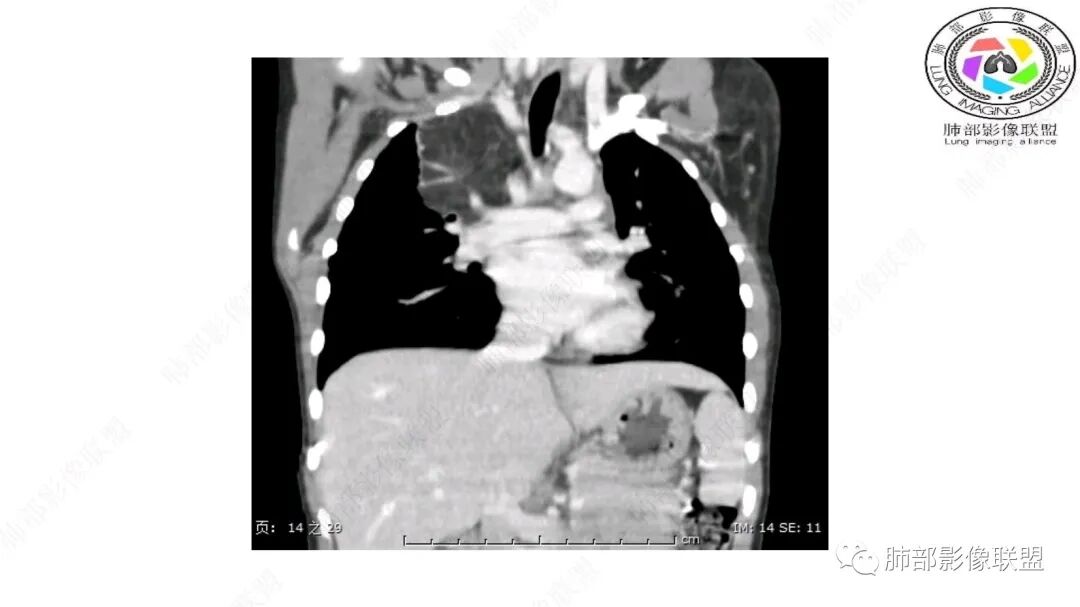

右纵隔团状,密度不均,脂肪密度为主,内可见腺体样组织,类似乳腺,病灶边缘有分叶,与胸腺关系密切,增强后血管穿行。考虑胸腺脂肪瘤(不典型垂乳征),鉴别畸胎瘤。

三岁小儿,右侧纵隔巨大脂肪密度肿块,肺动脉穿行其中,密度欠均匀,未见明确实性成分,纵隔脂肪母细胞瘤,冬眠瘤鉴别纵隔脂肪增多症(多弥漫对称)。

右肺门上方,位于纵隔胸膜旁见巨大肿块,脂肪为主混合密度,内见细小血管影,肿块最大长径与纵隔胸膜平行,包绕右肺上叶肺动脉,右肺上叶及纵隔结构推压,无侵蚀破坏,良性肿瘤,起源纵隔胸膜血管平滑脂脂肪瘤。

病灶属于交界区,主体位于肺内,占位效应明显,前方突入胸壁,胸腺受压变形,胸膜显示欠清楚;病灶包绕上叶肺动脉;似乎有体动脉供血。符合肺内的点:包绕上叶肺动脉分支;符合纵隔的点:前方似乎突入胸壁,与胸腺关系比较密切,但是与上腔静脉的关系提示病灶不支持纵隔来源,前纵隔的常规会将上腔静脉受压后移、外移,这是不符合的。

1.右上肺-纵隔交界区巨块影,主体位于右肺一侧,紧贴胸腺、头臂干、右锁骨下动脉、上腔静脉、奇静脉等,不能分离,但病灶整体边界清楚。注意上述相邻腔静脉等结构未见受压变形,纵隔亦未见明显向左推移,至少提示两点:

2.肺动脉穿行也许是肺内来源最重要支持点!

脂肪母细胞瘤由成熟程度不同的脂肪组织、纤维间隔、黏液基质、小血管丛等间质成分组成,以脂肪组织与黏液样基质为主,其影像学表现取决于上述组织成分。典型的CT和MRI表现为:前后纵隔均可发生,常见于前纵隔;肿块大小不一,直径多在3cm~7cm,密度均匀,CT值呈水样或脂肪密度,脂肪组织密度或信号为主的肿块,其内密度或信号不均匀,可见粗细不一的分隔影,且有结节、片状影,后者可呈轻中度强化;结节状肿瘤包膜完整;弥漫性者包膜不明显,常呈浸润性生长;周围结构为受压和推移改变,可有少量胸腔积液,淋巴结无增大。